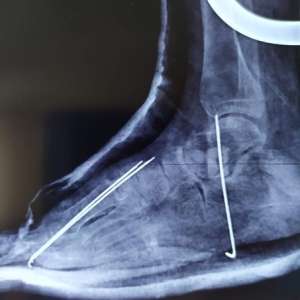

В Кирове вылечили 11-летнего мальчика, который не мог самостоятельно ходить

Мальчик с ДЦП попал в клинику в январе. У ребенка диагностировали ограничения движения верхних и нижних конечностей, деформацию обеих стоп, которая прогрессировала с его ростом.

После двух операций стопы вывели в правильное положение, устранили ограничения на уровне коленных и голеностопных суставов, а также улучшился баланс мышц-антагонистов. Теперь ребенок может самостоятельно ходить.

Мальчика выписали на дальнейшее амбулаторное лечение.